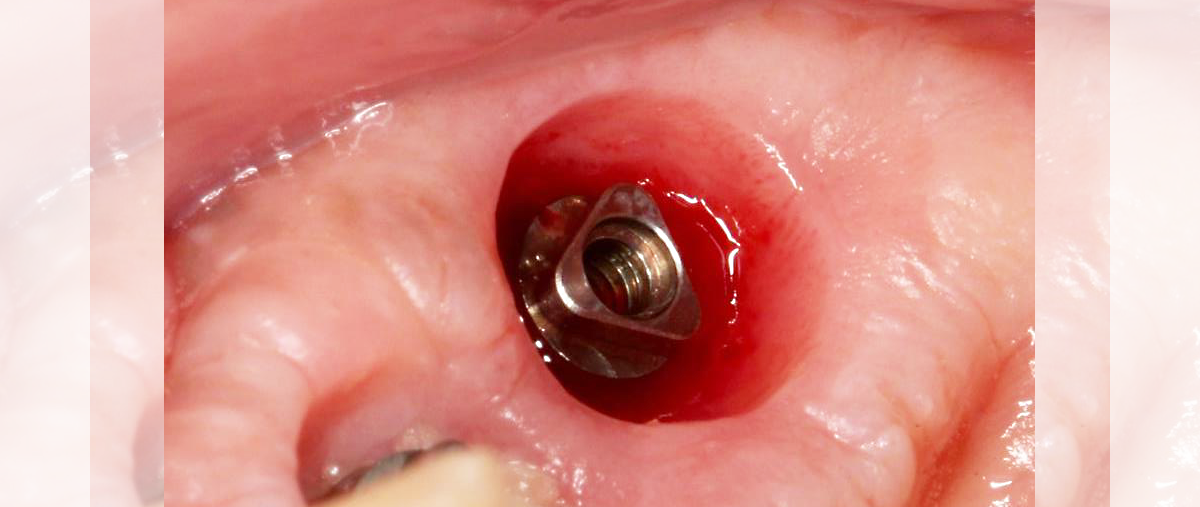

Sur le plan parodontal, la gestion du profil d’émergence a été revisitée de façon à favoriser le réaménagement d’un joint muqueux épais de première intention qui a vocation à jouer le rôle de barrière naturelle.

Le positionnement vertical de l’implant est légèrement modulable selon le biotype parodontal. L’interface prothétique est décalée au dessus du joint muqueux ; le risque de contamination iatrogène lors des phases de restauration prothétique est réduit.